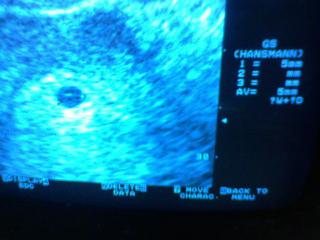

ahojte, tak 2.2. som bola u lekara, vsetko v poriadku, videl vak 5mm a v nom bodku, vraj malinke, este nevidel bit srdiecko, lebo to je len 5tt....chcel aby som prisla zasa o tyzden, ja som chcela az o tri tyzdne, tak sme sa dohodli na kompromise, ze pridem 16.2. to by uz mal vidiet bit srdiecko....moj gyn. nema ultrazvuk na usb alebo foto, tak povedal, ze si mam mobilom odfotit, ziadna vyhra, kedze mobil ma zly fotak...verim, ze sa bude vsetko vyvijat v najlepsom poriadku 🙂

ahojte.. hm.. mne povedal lekar, že moja bublinka má 13,2 mm.. alebo približne, už si nepamätám.. bola som v 5+3..

@tun1ska ahoj mne brali krv na hcg 30DC cize 27.1. a mala som ho 489, ak si to presne pamatam 🙂 ...na sone som bola 26.1., kde videl sliznicu 13mm a marilo sa mu, ze nieco vidi...2.2. videl vacok 5mm a v nom bodku a objednana som zase 21.2., ze uz by mal vidiet bit srdiecko 🙂 ...tak nech vsetko ide ako ma 🙂